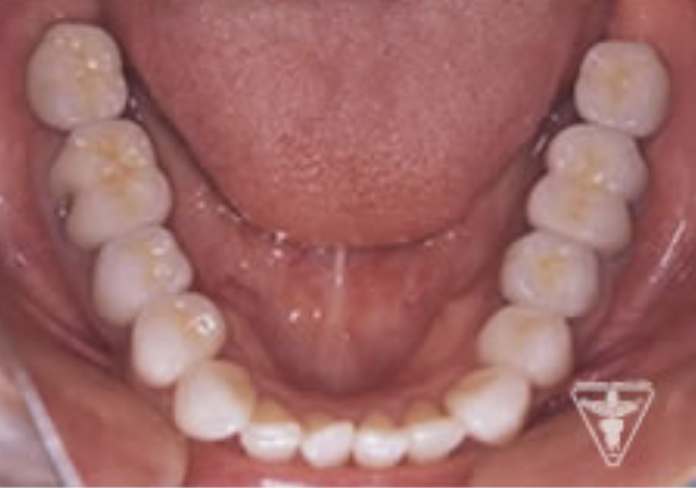

治療前

初診時の正面観・側方観・かみ合わせの面の状態を示します。

下の顎のずれがあるのを確認して下さい。